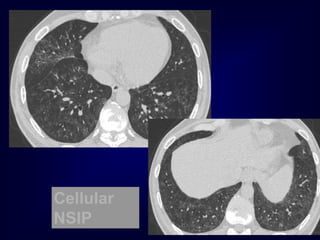

nonspecific interstitial pneumonia (NSIP)

DI

P

Cellular

NSIP